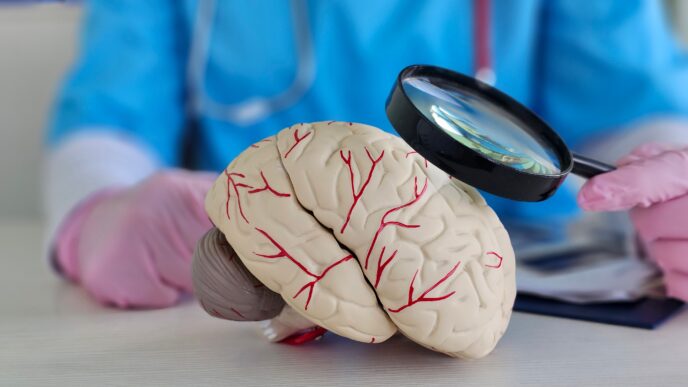

Športujúci ľudia môžu mať až o 45 percent nižšie riziko demencie. Rozhoduje však vek, v ktorom boli najaktívnejší

Učenie jazykov môže oddialiť Alzheimerovu chorobu. Ľudia hovoriaci dvoma jazykmi si udržujú mozog dlhšie v kondícii